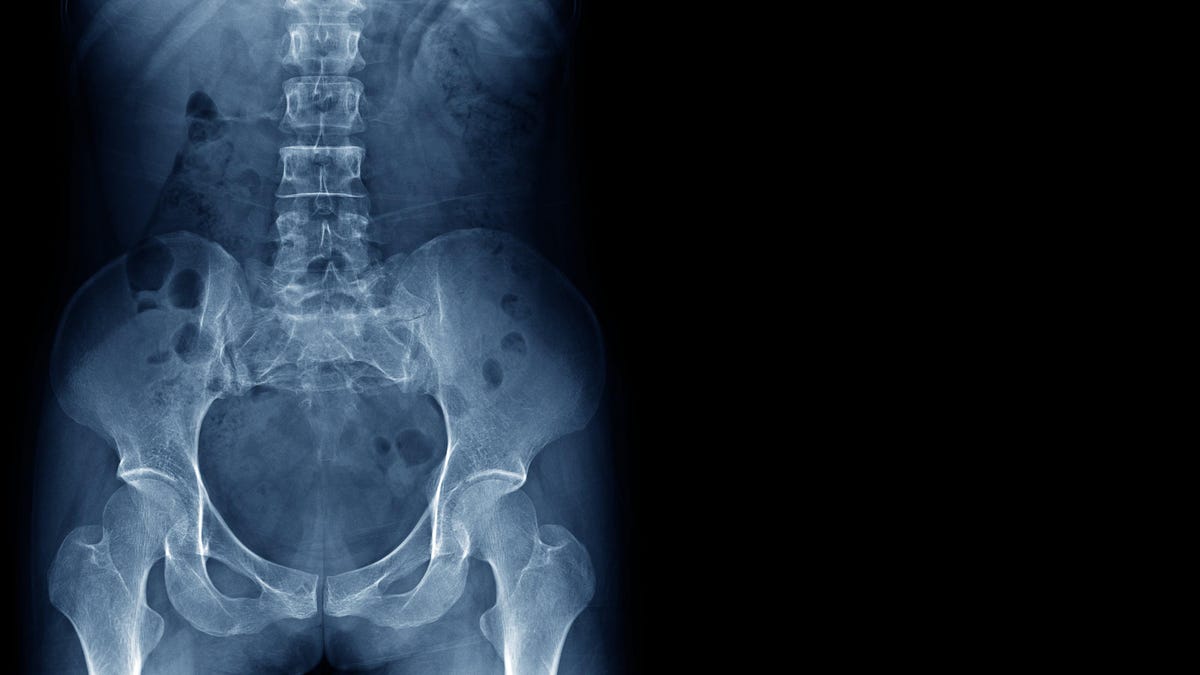

Όσο διασκεδαστικό κι αν φαίνεται το να είμαστε σχεδόν αβαρείς, το περιβάλλον μικροβαρύτητας του διαστήματος μπορεί να έχει βαθιά αρνητικές επιπτώσεις στο σώμα μας εάν παραμείνουμε εκεί πάνω για πολύ καιρό. Ιδιαίτερα τα οστά μας βασίζονται στην τακτική μηχανική καταπόνηση για να παραμείνουν υγιή, μεγάλο μέρος της οποίας προέρχεται από την καταπολέμηση της βαρύτητας της

ς. Χωρίς αυτό το άγχος, η παρ

αγωγή

κυττάρων που δομούν τα οστά (που ονομάζονται οστεοβλάστες) από το σώμα αρχίζει να επιβραδύνεται. Ζευγάρι

με τη συνεχή φθορά των οστών μας, αυτό οδηγεί σε

προοδευτική απώλεια οστού

, το οποίο μπορεί στη συνέχεια να αυξήσει τον κίνδυνο καταγμάτων κατά τη διάρκεια της αποστολής και πιθανώς ακόμη και αργότερα στη ζωή. Οι αστροναύτες μπορούν να χάσουν έως και 1% της οστικής μάζας τους για κάθε μήνα που περνούν στο διάστημα, ενώ η ανάκαμψη στη Γη μπορεί να διαρκέσει χρόνια μετά από ένα μακρύ ταξίδι.